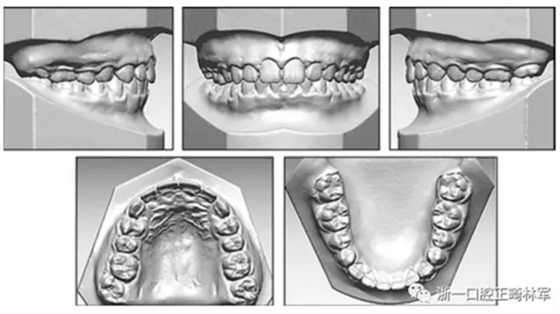

全口粘接托槽,第一磨牙粘接帶環(huán),同時焊接一個位于腭側(cè)牙齦上方的弧形硬絲。大約使用250g的力量掛鏈圈遠中移動牙列,如下圖所示。鏈圈每月更換一次。22個月后治療完成,粘接舌側(cè)保持器。